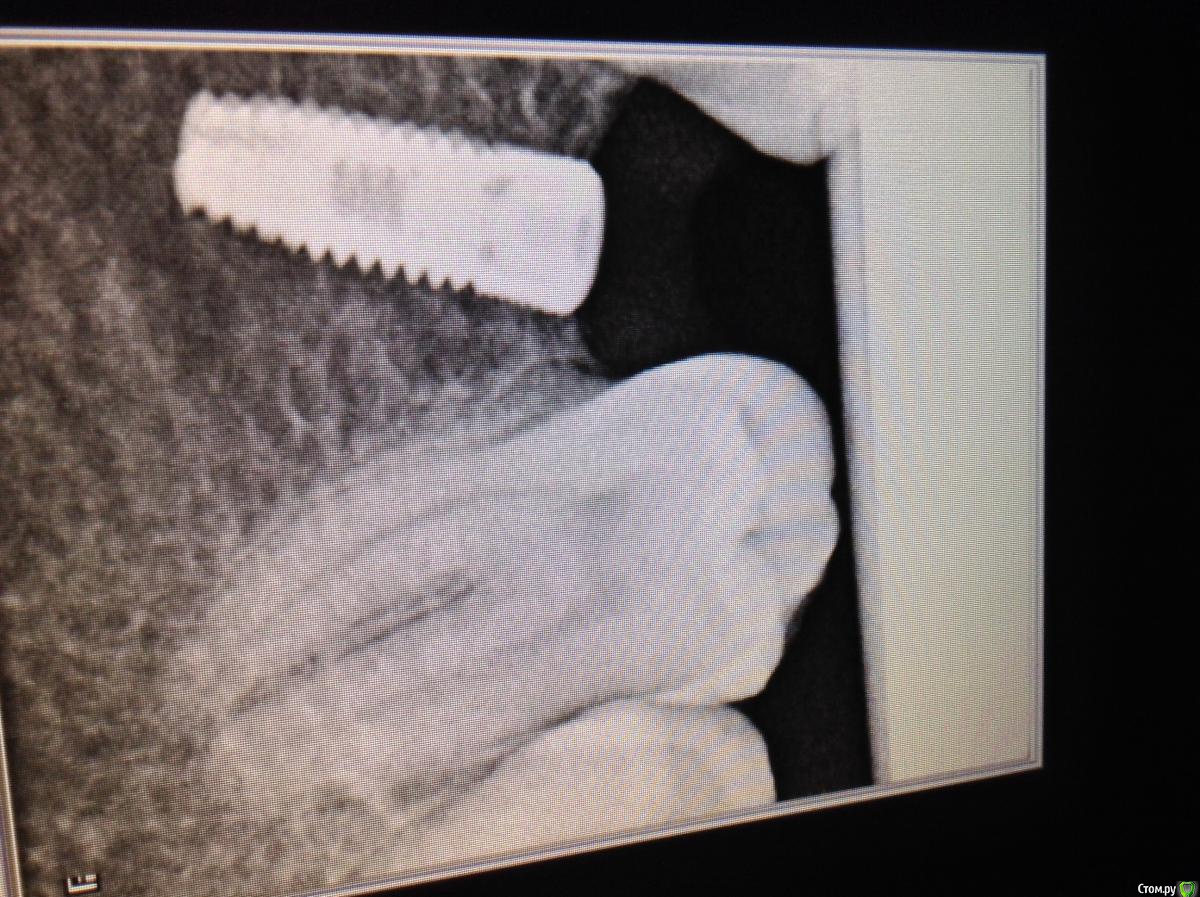

ksenistom Опубликовано 2 декабря, 2014 Поделиться Опубликовано 2 декабря, 2014 Уважаемые коллеги,подскажите пожалуйста,как быть в данной клинической ситуации? Ссылка на комментарий

ksenistom Опубликовано 2 декабря, 2014 Автор Поделиться Опубликовано 2 декабря, 2014 Почему места недостаточно?)) Все получится, даже у среднеграмотного техника. Где одиночка, премолярчик выйдет)Мне хирург так и сказал,только что мне с 6 делать?там все вплотную,расстояние должно 1,5мм минимум быть? Ссылка на комментарий

Dman Опубликовано 2 декабря, 2014 Поделиться Опубликовано 2 декабря, 2014 с планированием беда какая-то вышла) 1 Ссылка на комментарий

ksenistom Опубликовано 2 декабря, 2014 Автор Поделиться Опубликовано 2 декабря, 2014 с планированием беда какая-то вышла)[/quotпациент знакомый из другой клиники пришел,я уже результат получила((( Ссылка на комментарий

Heatshock Опубликовано 4 декабря, 2014 Поделиться Опубликовано 4 декабря, 2014 хирургический шаблон явно не в почете у хирурга) Ссылка на комментарий